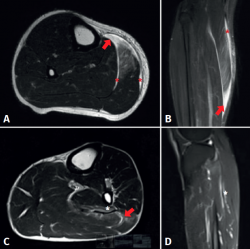

Figure 3. Magnetic resonance imaging study of triceps surae injuries. A: T2 axial sequence; B: coronal STIR sequence showing a fibrillar defect (red arrow) in the myotendinous junction of the medial gastrocnemius muscle, associated to a haematic collection in the peri-aponeurotic plane (red asterisks); C: T2 axial sequence; D: T2 FS sequence showing a fibrillar defect of the soleus muscle in the lateral proximal myotendinous junction (red arrow) associated to oedema of the adjacent muscle fibres (white asterisks).